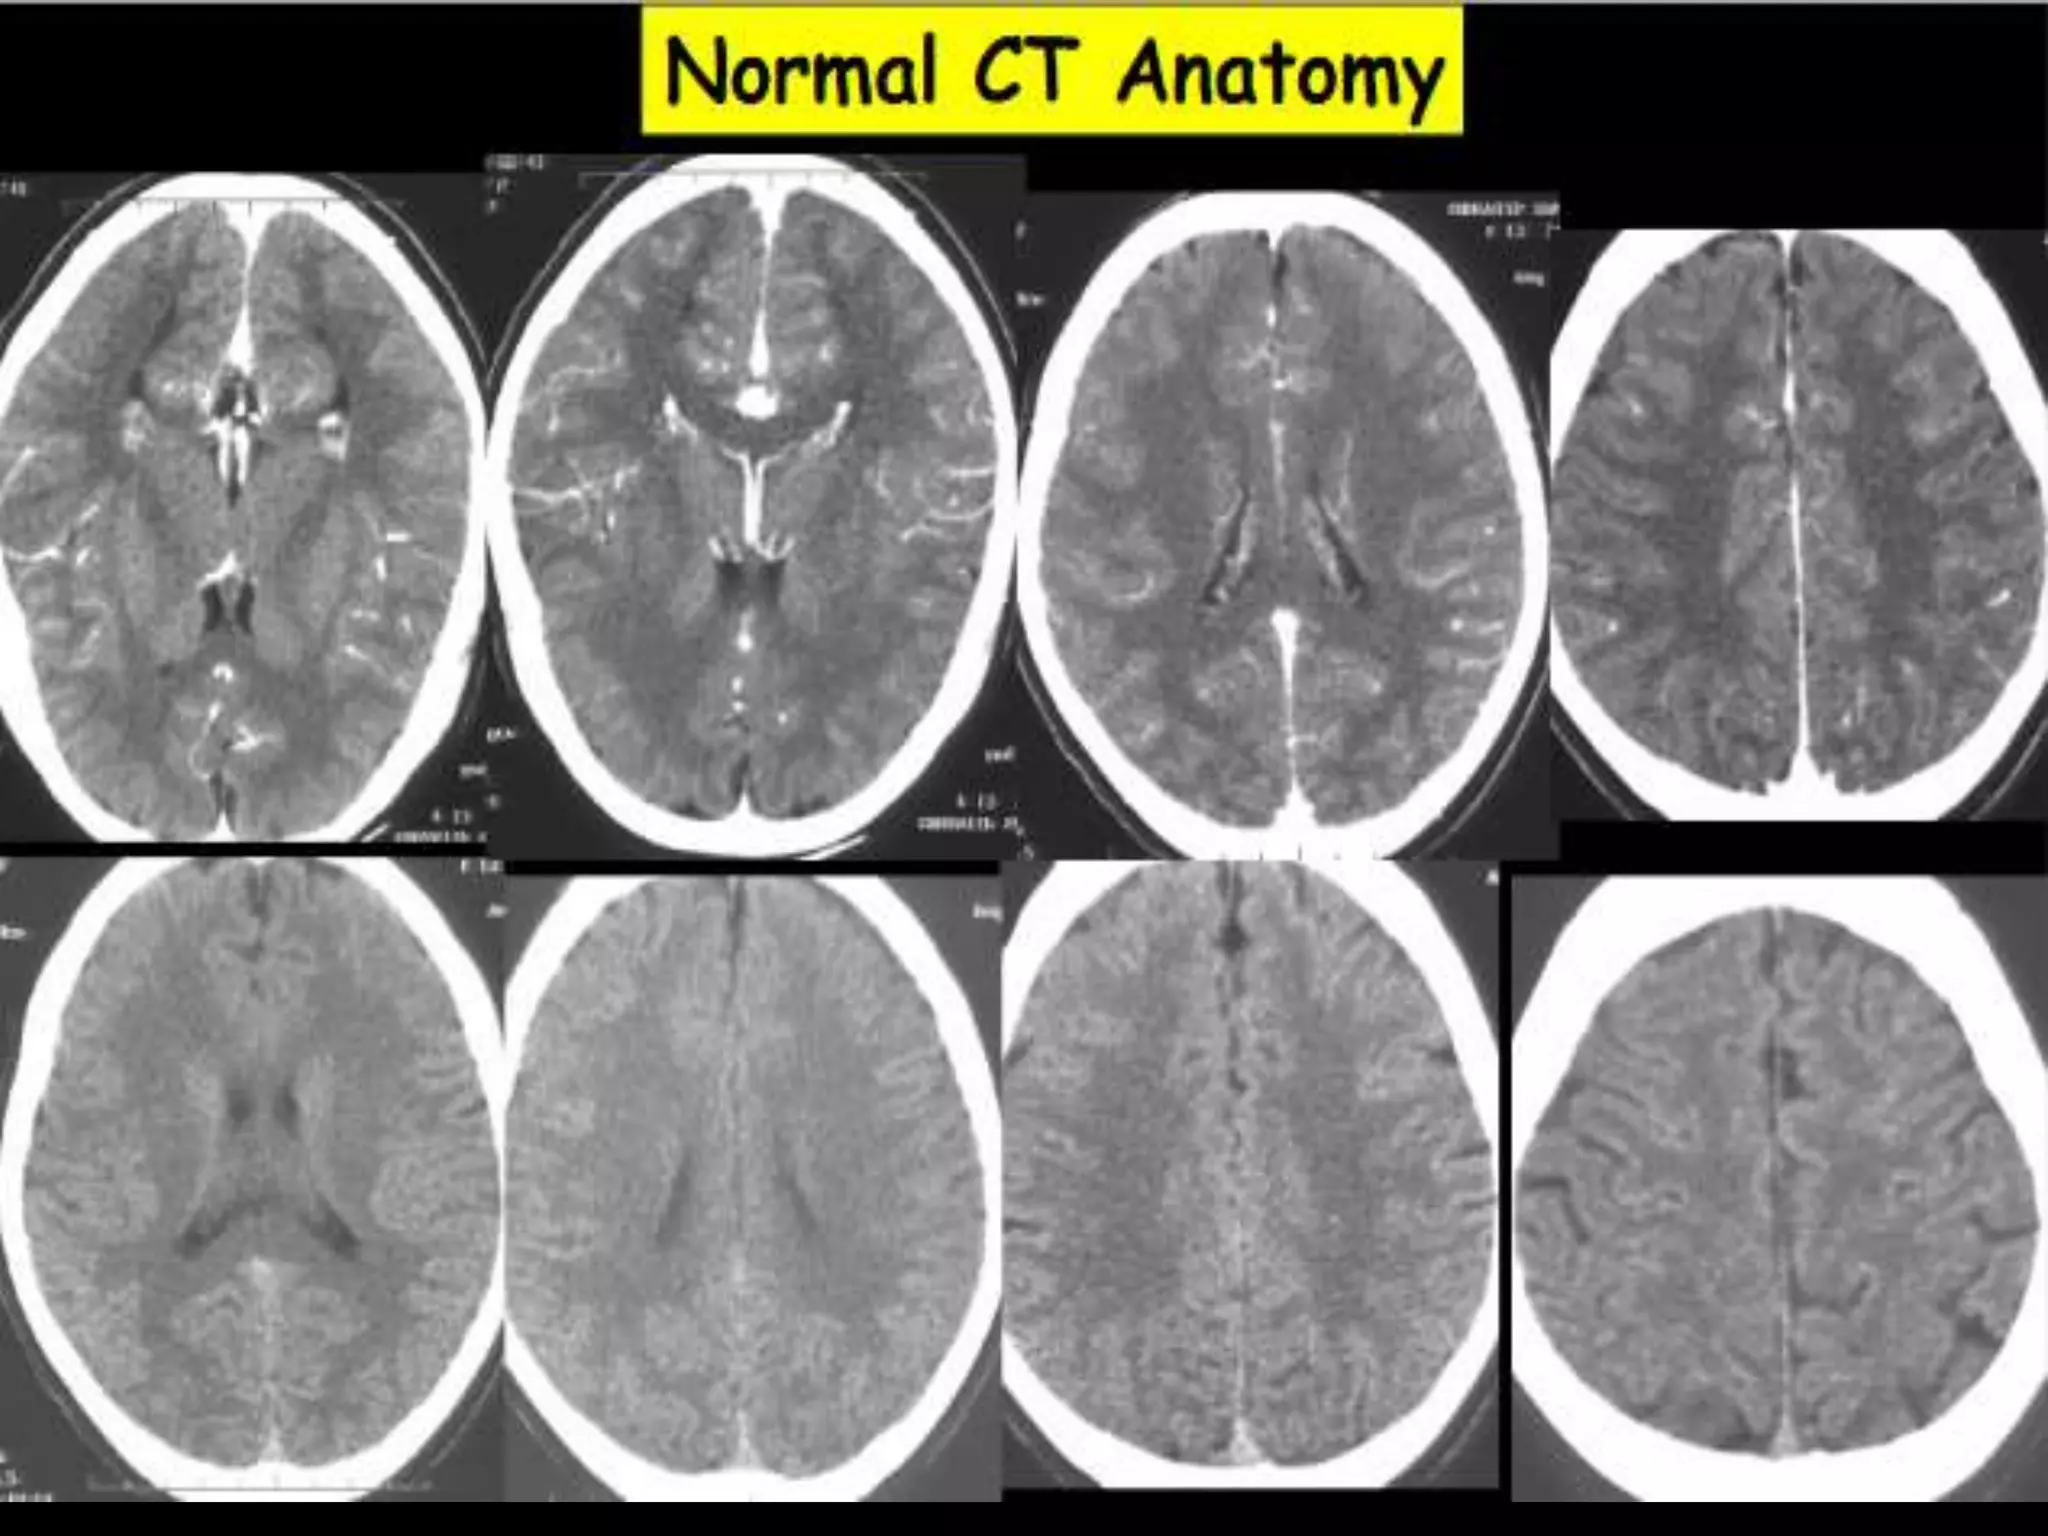

Axial CT Anatomy.

Sectional Anatomy: NormalAxial CT and MRI Anatomy. On CT and MR scans, the brain has been briefly viewed in infratentorial and supratentorial sections, as described below. CT scans are performed with a 15- to 20-degree angulation to the canthomeatal line at 8-mm increments. MRI scans are generally obtained parallel to the AC-PC line in the axial plane with 6-mm slice thickness. Using the sagittal view, the coronal sections are acquired parallel to the brain stem, and the sagittal sections are obtained perpendicular to the axial section. On MRI studies, cranial nerves IX and X can be demonstrated at this level because they emerge from the postolivary sulcus. The posterior aspect of the cerebellar hemispheres is outlined by the inferior portion of the cisterna magna.